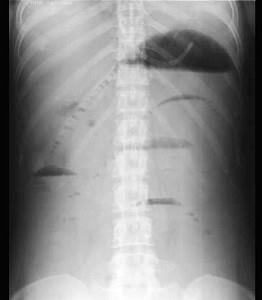

问题 机械性肠梗阻,腹部平片中显示下列何项变化时应考虑绞窄性肠梗阻的可能 ( )

选项 A、孤立肠段扩张且较固定 B、以上都不是 C、扩张肠段呈梯形排列 D、扩张肠段粘膜呈鱼刺状 E、近端肠段扩张,远端肠腔未见气体

答案 A